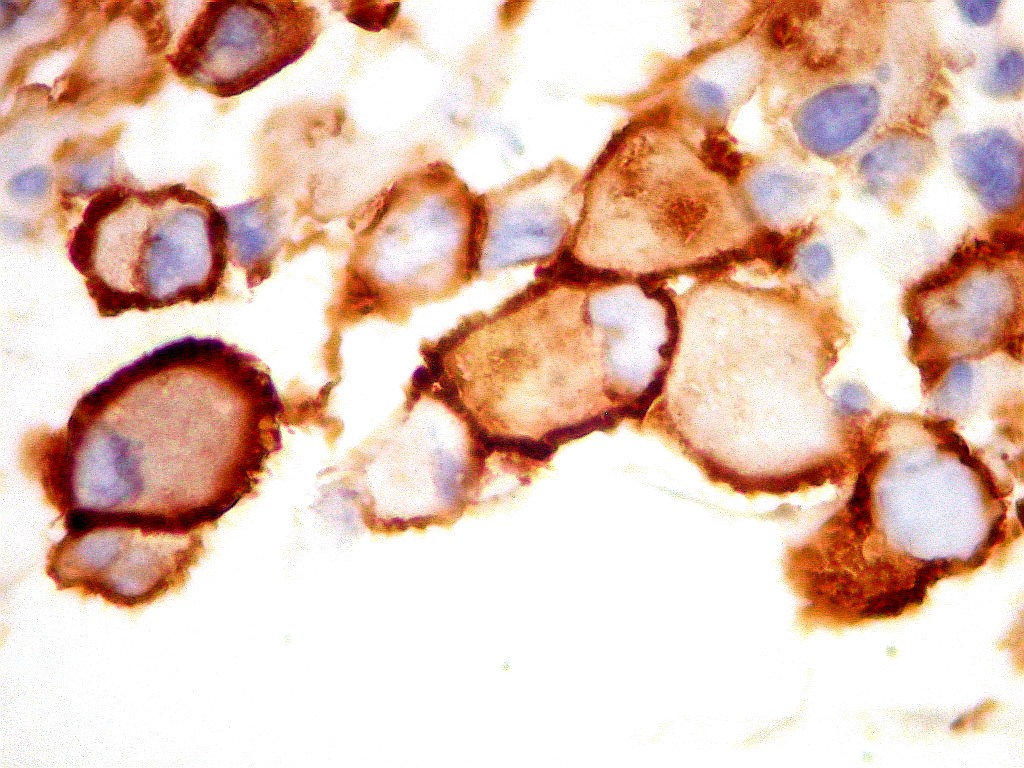

Sinaptofisina.     SNF, um marcador de neurônios, foi positiva no citoplasma em parte das células neoplásicas deste ATRT, enfatizando a expressão multifenotípica dos antígenos neste tumor.

Células  SNF negativas.